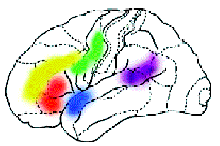

|

Исследования, проведённые в последние годы в Институте

мозга человека Российской академии наук, позволили определить, какие области

мозга отвечают за осмысление различных особенностей воспринимаемой человеком

речи: за грамматику, синтаксис, орфографию и другие.

Область, отвечающая за определение грамматических

характеристик слова

Зона, активная при необходимости использования

кратковременной памяти

Зоны речевой моторики

Зоны первичной обработки цвета

Зона орфографической обработки слов

Область, участвующая в сознательной и непроизвольной

обработке смысла слов

Области, предположительно управляющие подавлением

обработки речевых признаков в задаче на обработку физического признака слова,

например цвета